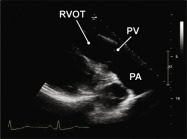

| 2.5. Mặt cắt trục dài cạnh ức qua đường ra thất phải |

||||||||

Cửa sổ siêu âm cạnh ức

Mặt cắt trục dài cạnh ức Ngửa và xoay đầu dò về phía đường ra thất phải/ |

Đường ra thất phải (RVOT) Van động mạch phổi (PV) Động mạch phổi (PA) |

|||||